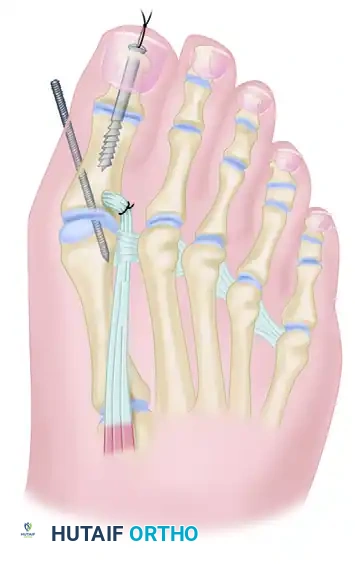

Surgical Technique: The Johnson and Spiegl Procedure

The procedure is performed under regional or general anesthesia with a well-padded calf or thigh tourniquet to ensure a bloodless surgical field. The patient is positioned supine with a bump under the ipsilateral hip to internally rotate the leg to a neutral position.

Step 1: Incision and Exposure

Begin with an L-shaped incision to maximize exposure of both the MTP and IP joints while respecting the dorsal angiosomes of the hallux.

- Initiate the incision in the first web space, between the midportions of the first and second metatarsals.

- Extend the incision distally along the dorsolateral aspect of the great toe.

- Curve the incision medially as it approaches the insertion of the EHL tendon at the base of the distal phalanx.

Step 3: Preparation for Interphalangeal Joint Arthrodesis

With the EHL detached, the IP joint is easily accessed.

- Perform a transverse arthrotomy of the IP joint.

- Acutely flex the distal phalanx to expose the articular surfaces of both the head of the proximal phalanx and the base of the distal phalanx.

- Using a microsaw or rongeur, resect the articular cartilage down to bleeding subchondral bone. The cuts should be flat and parallel to permit a neutral position in both the sagittal and coronal planes.

Step 4: IP Joint Fixation (Shives and Johnson Technique)

Rigid internal fixation is paramount for a successful arthrodesis. The use of a 4.0-mm cancellous lag screw, as advocated by Shives and Johnson, provides excellent compression and rotational stability.

- Retrograde Drilling: Drill a 2.0-mm diameter hole longitudinally in a retrograde manner starting at the center of the denuded articular surface of the distal phalanx.

- The drill bit should exit the skin at a point exactly 5 mm plantar to the tip of the nail in the midline of the toe.

- Antegrade Drilling: Appose the denuded articular surfaces of the proximal and distal phalanges in neutral alignment. Insert the drill bit distally at the tip of the toe (through the previously created exit hole) and advance it proximally.

- Follow the previously placed retrograde hole, cross the IP joint, and drill into the base of the proximal phalanx, advancing down the center of its medullary canal.

- Overdrilling and Tapping: To achieve a true lag effect, overdrill the distal phalanx (the near cortex) with a 2.7-mm drill bit to create a gliding hole. Tap the entire drill path with a 3.5-mm tap to prepare for the cancellous screw.

- Screw Insertion: Following the drill path in a proximal direction, insert a 4.0-mm partially threaded cancellous bone screw.

- As the screw head engages the distal phalanx, the lag effect will produce robust compression across the arthrodesis site, ensuring firm fixation.

Step 5: EHL Tendon Routing and Transfer

With the IP joint securely fused, attention is turned to the dynamic correction of the MTP joint. The goal is to route the EHL tendon to act as a lateral collateral ligament substitute and a plantarflexor.

- Identify the deep transverse metatarsal ligament in the first web space.

- Pass the mobilized EHL tendon plantar to the deep transverse metatarsal ligament. This critical step changes the vector of the EHL pull from dorsal-medial to plantar-lateral.

- Route the tendon dorsally to the base of the proximal phalanx.

- Prepare a drill hole through the base of the proximal phalanx from lateral to medial. Pass the EHL tendon through this osseous tunnel.

- Apply tension to the EHL tendon while holding the MTP joint in approximately 10 to 15 degrees of extension and neutral coronal alignment (correcting the varus).

- Suture the tendon back onto itself using non-absorbable braided suture (e.g., #2-0 FiberWire or Ethibond) to secure the transfer under appropriate physiological tension.

- Obtain intraoperative fluoroscopy (AP, Lateral, and Oblique views) to confirm the concentric reduction of the MTP joint, the correction of the varus angle, and the optimal placement and compression of the 4.0-mm IP joint screw.